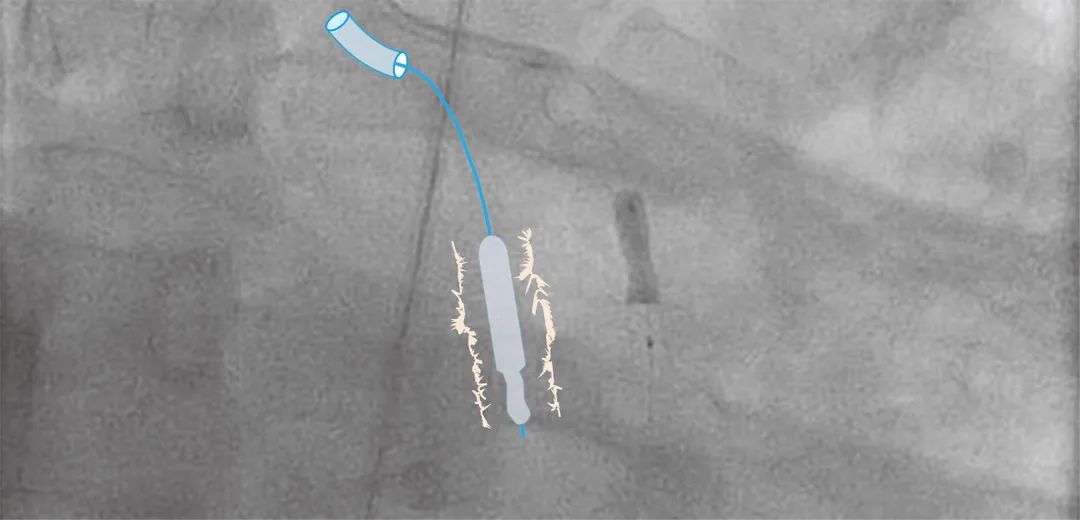

2.2刺破被困球囊

可以使用子导管刺破球囊。将子导管的头端切下约5mm。切断的目的不是使导管头端变锋利,而是露出子导管中的编织钢丝。当暴露的钢丝抵住球囊尾部时,球囊会被刺破。因此,暴露的钢丝越多,该技术的成功率就越高。由于采用了编织钢丝,实施该技术时,强烈推荐使用5 Fr ST01(Terumo, Tokyo)作为子导管。沿着球囊杆和导丝,将子导管送入母导管中,同时用无法回缩的球囊进一步锚定,以提升子导管推送能力。如果球囊位于冠脉远端,子导管可能无法到达球囊附近。应提前将常规Y型阀更换为短型Y型阀。如果无法通过推送子导管头端使球囊破裂,则可以稍微旋转子导管。延长导管通常无效,因为它们无法提供足够的推力或旋转操作。此外,需要注意的是,将头端被切断的子导管送入冠脉会增加冠脉损伤的风险。如果球囊位于冠脉近端,则可以将母指引导管深插。但是,如果球囊位于冠脉远端,则子导管头端无法被母指引导管保护,这需要更小心仔细的操作。

将Heartrail II 5 Fr ST01导管(Terumo)的头端切断以露出钢丝,并将其作为子导管送入母导管中。将子导管靠近球囊,并将其头端抵在球囊上以使其被刺破。如果球囊位于远端,子导管可能无法到达。因此,应提前将常规Y型阀更换为短型Y型阀。如果无法通过推送子导管头端使球囊被刺破,则可以稍微旋转子导管